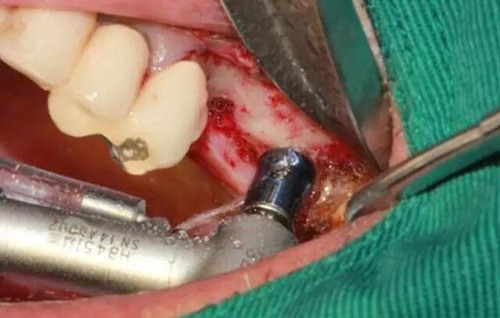

MASAL工具內(nèi)提升永磁鉆--這就是本病例改良開窗的關(guān)鍵

安全地在上頜竇外壁鉆一個洞

分離洞邊緣膜

CAS水壓剝離頰側(cè)竇膜(安全省事)

開窗永磁鉆